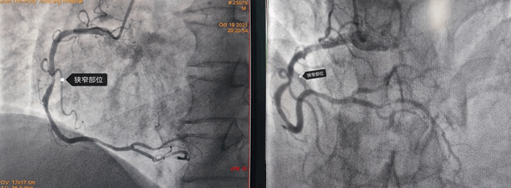

2021年10月19日,64歲的馬先生因胸悶、心悸等癥狀入住心血管九病區,馬先生有高血壓、吸煙等冠心病危險因素,心電圖有心肌缺血表現,為明確馬先生是否為冠心病所致上述癥狀以及決定下一步診治方案,給他進行了冠脈造影檢查,結果如下圖:

造影結果右冠多處狹窄約70-90%,左冠也是多處70-80%狹窄;對于這樣一個結果,是這些狹窄造成的胸悶、心悸嗎?這些病變需不需要都給予介入處理呢?一根血管植入支架還是三根血管都需要植入支架?心內九科崔旭輝主任帶領介入醫生團隊討論后,決定進行RFR檢查給出一個明確的答案。所以經過與患者及其家屬溝通后選擇進行RFR檢測,結果如下圖: